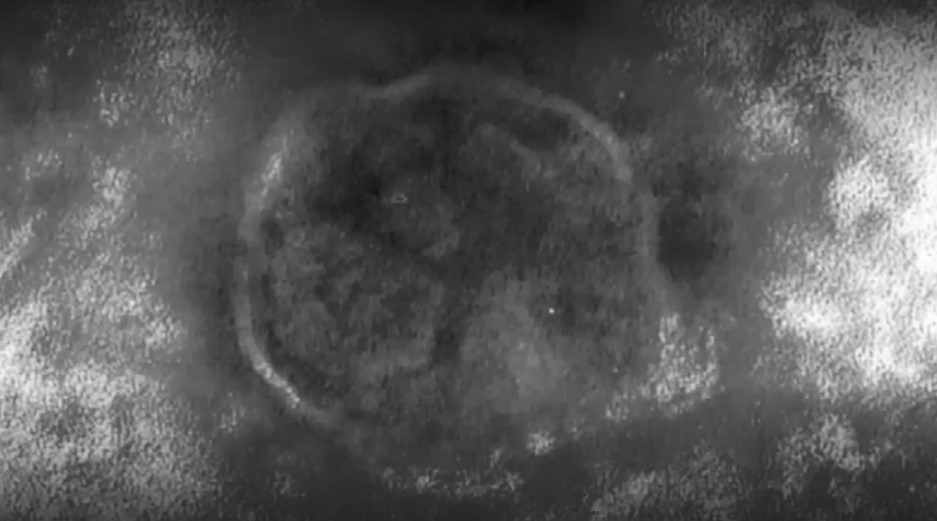

26日、福岡で感染確認が発表された「はしか」です。